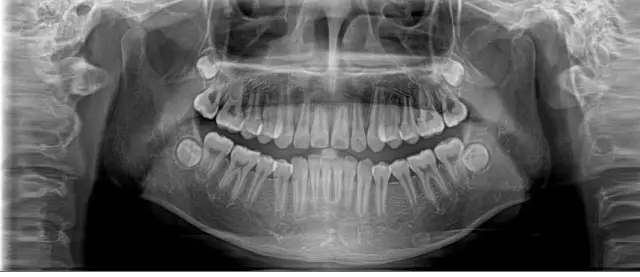

全景片就是可以在一张胶片上可以完整、清晰地显示上颌骨、下颌骨全貌,上下颌牙列情况,牙槽骨情况,能清晰显示上颌窦腔、窦壁、窦底情况,以及颞颌关节情况,并对颌骨周围疾病的诊断提供帮助。

因为全景片可以精确测定牙齿倾斜角度、牙周软组织情况、牙根情况、牙槽骨质情况,解剖形态的精确测量为医生术前的诊断分析与设计提供全景样图像依据,口腔医生借此能更好地为患者设计治疗方案。

拍摄全景片是口腔治疗之前很重要的一个检查过程,医生通过全景片可以观察到牙齿的健康状况,是否有隐形龋齿、埋伏阻生牙、多生牙、牙槽骨吸收、牙龈萎缩、口腔内是否长有瘤体等。在做牙齿种植、牙齿矫正、牙齿修复、智齿拔除等之前,均需要拍摄口腔全景片。